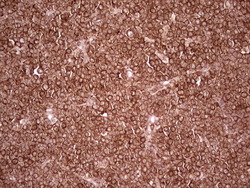

- Main image

- Experimental details

- Immunohistochemical staining of paraffin-embedded Human lymphoma tissue using anti-WIBG mouse monoclonal antibody. (Heat-induced epitope retrieval by 1 mM EDTA in 10mM Tris, pH8.5, 120C for 3min, TA806496)

- Validation comment

- IHC